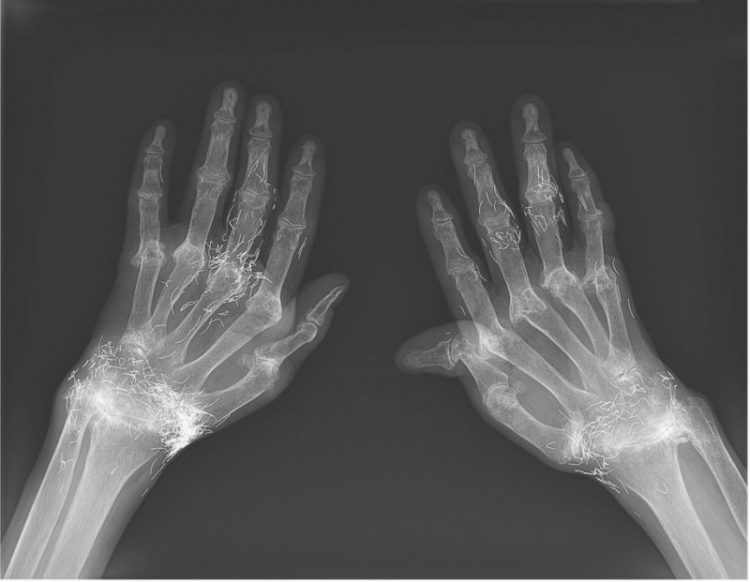

Photo: Dr Young-Bin Joo and Dr Kyung-Su Park/New England Journal of Medicine

Gold thread acupuncture has long been used in Asian countries to treat various types of pain. The procedure is usually performed by a person with no medical training and involves the permanent implantation of tiny threads of gold in painful areas of the body, using acupuncture needles. Apparently, the insertion of these sterile pieces of gold is believed to result in continuous stimulation inside the body, and pain relief. There is no evidence that this alternative pain relief treatment actually works, but doctors have reported several complications related to the procedure.

The migration and fragmentation of gold threads inside the body of the patient are both possible over long periods of time, which can result in intense pain. Because this procedure involves the implantation of dozens, sometimes hundreds of tiny gold threads, the removal of all the inserted material is virtually impossible and may cause severe pain.